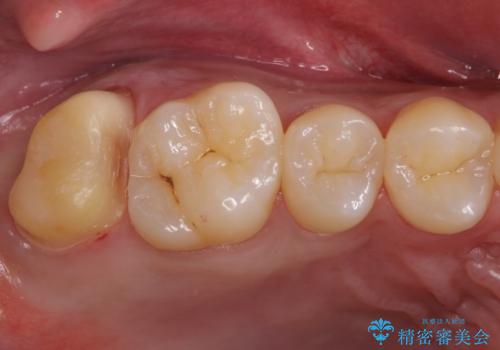

銀歯をなくしたい ジルコニアクラウンでの修復

- 銀歯を白くしたいとのことで来院されました。

歯を覆っている銀の詰め物の面積が広く、セラミックで同じ形態にすると強度に不安が残るため被せ物での修復処置を行っていきます。